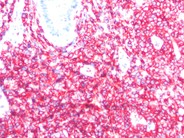

T-prolymphocytic leukemia cutis - 1.

Low-magnification view of skin biopsy from a patient with a diagnosis of T-PLL. There are both perivascular and diffuse dermal infiltrates without epidermatotrophism.